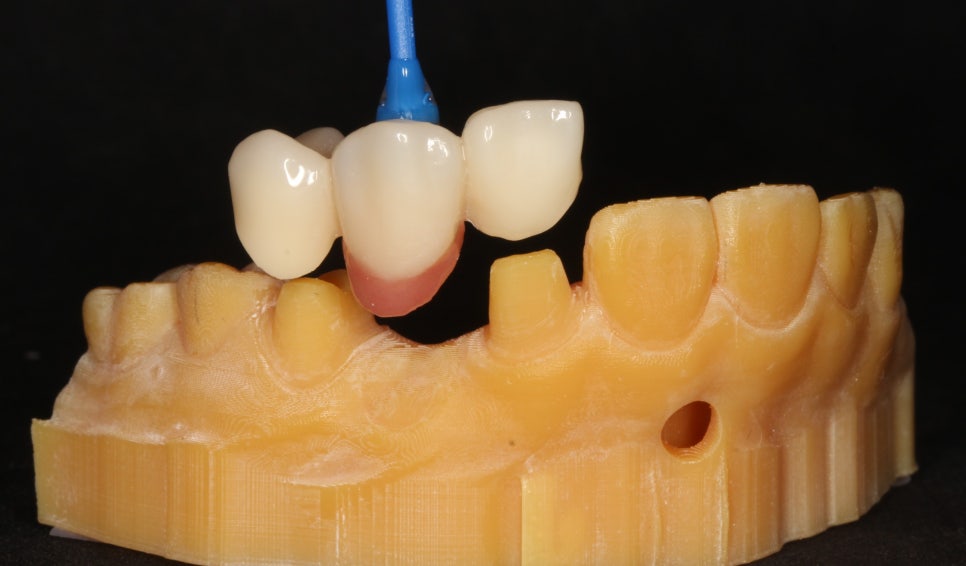

잇몸 뼈가 부족해 임플란트가 불가능한 치아에 미니쉬브릿지를 적용, 자연 치아의 모양과 기능을 대신했습니다.

발치 후 미니쉬브릿지 적용한 모습

임플란트 없이도 튼튼한 작은 앞니를 만들어낸 것이죠. 치아를 코팅하는 과정에서 치아의 손상된 형태나 색상, 앞으로 뻗쳐있던 각도까지 개선했습니다. 각 치아의 크기를 재분배해 벌어졌던 공간도 닫을 수 있었습니다.